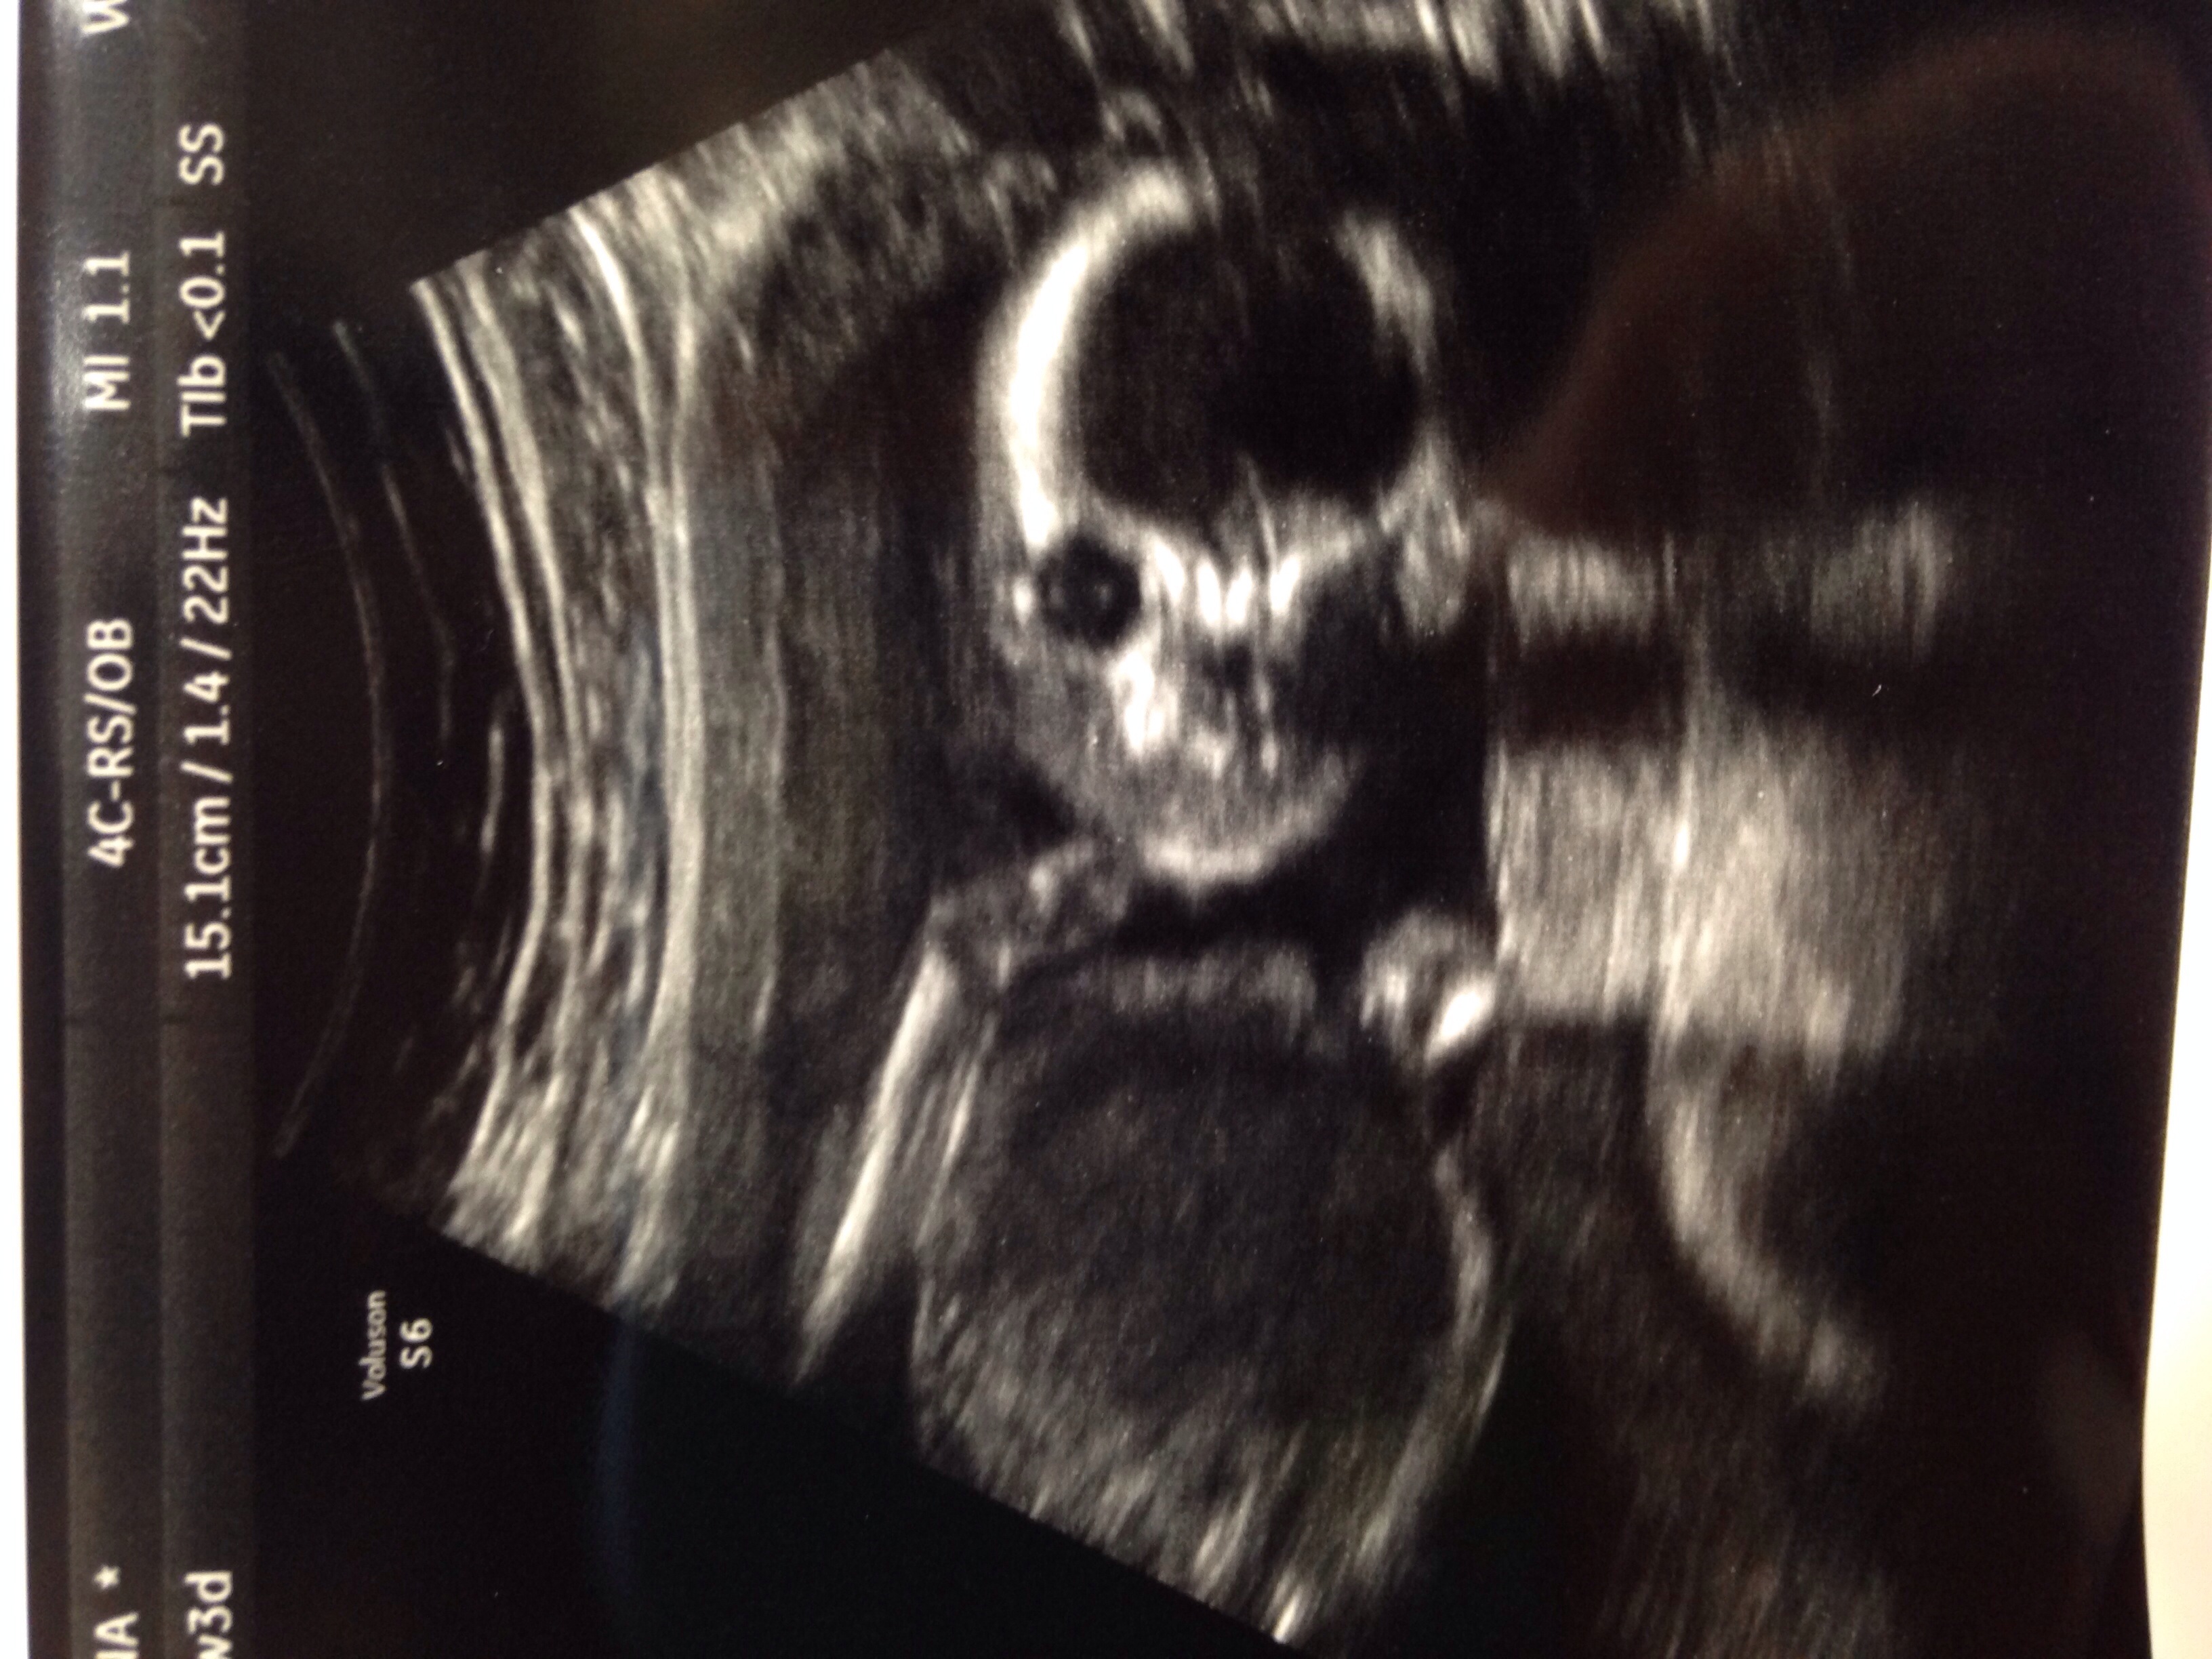

• So, I just got home from my A/S and baby is big and healthy! (baby has a big head too haha) Baby is very active and was kicking up a storm on the monitor. lol It looked like the baby was waving too. hehehe I cried before the A/S, during and I'm crying now after seeing my little nugget. I just can't believe this is happening.

And....

image

lol it's another boy!!! 3 boys and 1 girl. DW and I are thrilled :)